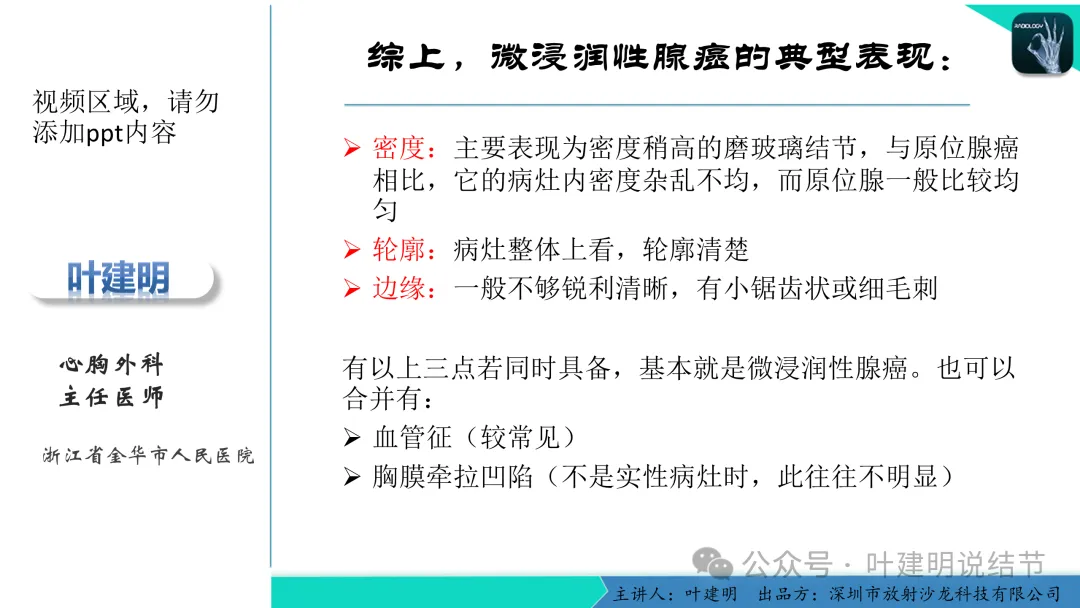

早在2020年时,我受邀在《放射沙龙》做过一个系列的精品课,当时专门总结分析过各类良恶性肺结节与肿块的影像特征,这是当时关于微浸润性腺癌影像特征的分析,今天看来仍基本不太需要改变,大家有兴趣的可以参考: